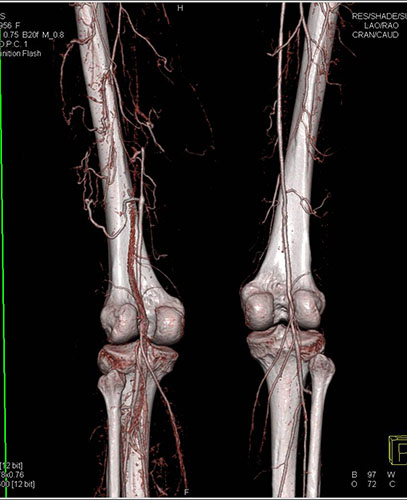

Απεικονιστικές εξετάσεις για τη διερεύνηση της διαλείπουσας χωλότητας αποτελούν το έγχρωμο duplex (triplex), η αξονική αγγειογραφία, η μαγνητική αγγειογραφία και η ψηφιακή αφαιρετική αγγειογραφία.

Διακρίνεται σε νόσο άνωθεν και κάτωθεν του βουβωνικού συνδέσμου, αναλόγως των αρτηριών που προσβάλλει στον καθένα καθώς και σε νόσο των κνημιαίων αρτηριών. Κλινικά εκφράζεται είτε ασυμπτωματικά, είτε ως διαλείπουσα χωλότητα ή ως κρίσιμη ισχαιμία. Διαλείπουσα χωλότητα είναι το άλγος στα κάτω άκρα που εμφανίζεται επαναλαμβανόμενα μετά από βάδιση ή άλλη φυσική δραστηριότητα.